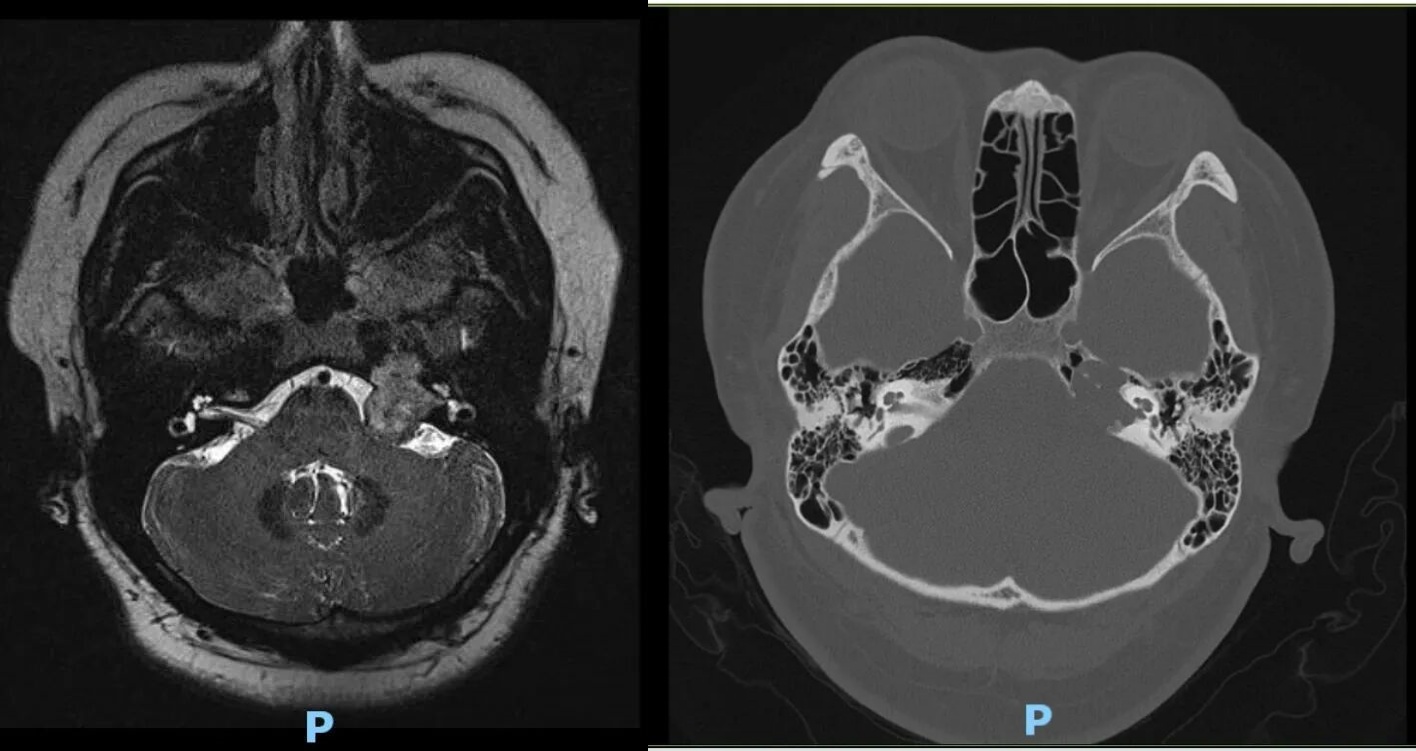

肿瘤位于桥小脑角,突入内听道,进入岩骨

术后核磁